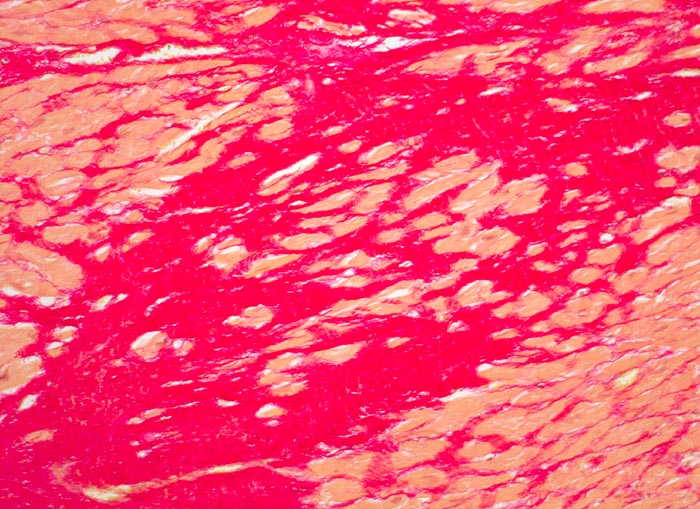

• Herdförmiger Ersatz der Muskulatur durch zellarme rote Kollagenfaserbündel.

• Hypertrophiezeichen der Herzmuskulatur im Randbereich der Narbenareale (verdickte Herzmuskelzellen mit vergrösserten hyperchromatischen Kernen).

• Im untersten Biopsiefragment sind die Narbenareale bandförmig subendokardial verteilt. Zwischen Narbengewebe und Endokard findet sich eine schmale Schicht erhaltener Muskelzellen (Ernährung dieser Zellen per Diffusion direkt aus dem Herzblut).